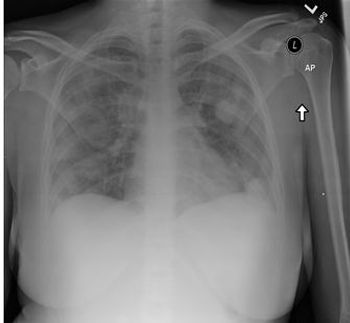

Undiagnosed lung disease in smokers, the impact of guidelines for community-acquired pneumonia in children, and climate change and asthma attacks make headlines in the respiratory news.

Respiratory disease is the main reason why patients visit primary care practices. This brief summary highlights the latest in research and patient care.